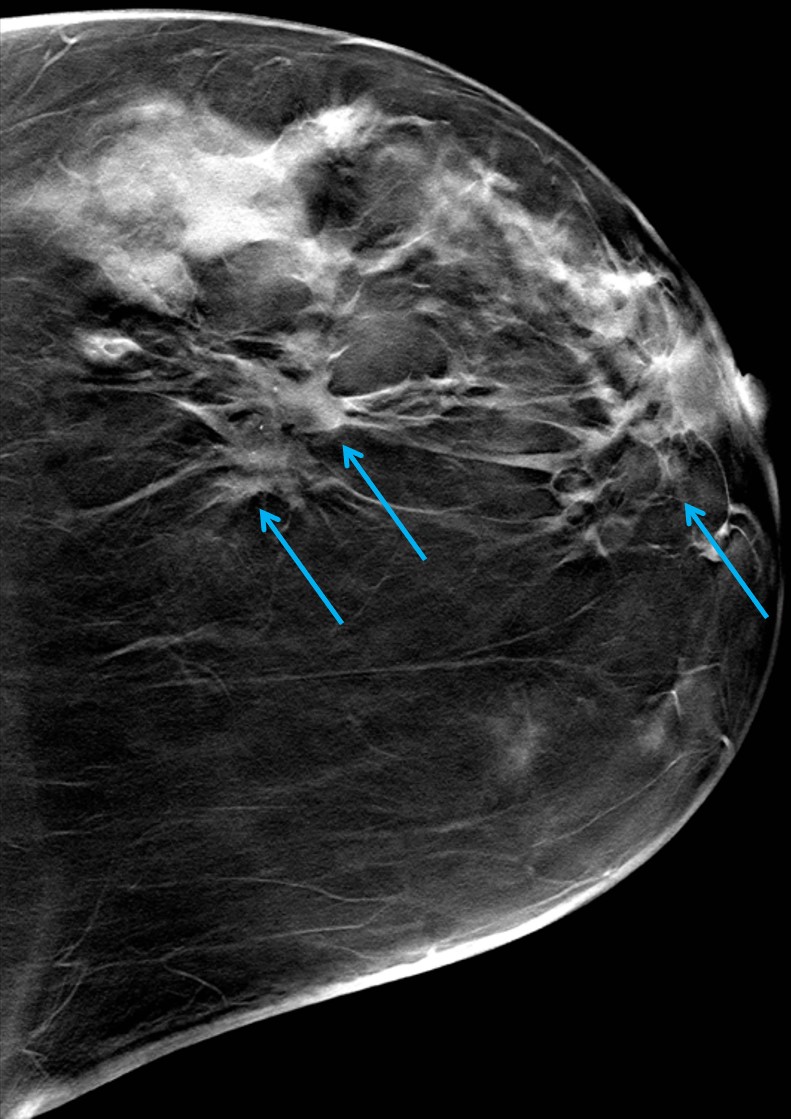

The most common cause of skin metastases in adult women is primary breast carcinoma, which comprises about 70% of cases [1]. Skin metastases have non-specific clinical appearances, making it challenging to differentiate them from other benign conditions [1]. We present a case of a 52-year-old female with type II diabetes and a three-month history of refractory skin lesions who did not respond to anti-inflammatory treatment. The patient subsequently complained of a right breast lump, evaluation of which led to the diagnosis of bilateral synchronous invasive lobular carcinoma.